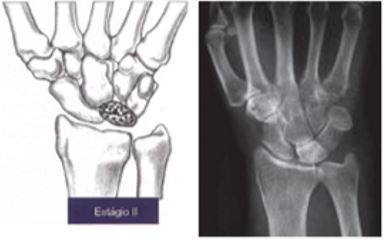

Como é o estágio II de Lichtman

A

• ESCLEROSE

ou

Múltiplas linhas de fratura

• melhor visto no Rx em perfil